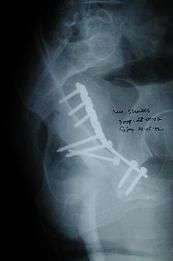

Posterior column fracture

Cause: as with posterior wall injury, this also occurs due to dash board injury.

How to diagnose: Best seen in iliac oblique and obturator oblique views

If the fragments do not fall into place, or if there are bone pieces in the joint, or if the joint is unstable, surgical fixation using screw(s) and plate(s) is performed